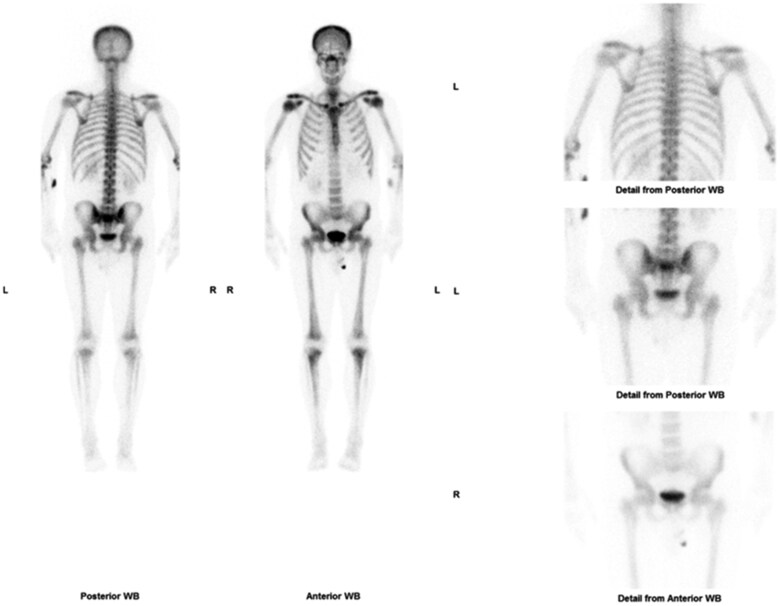

Skeletal mastocytosis as a cause of chronic widespread pain.

骨骼肥大细胞增多症是引起慢性广泛性疼痛的原因。